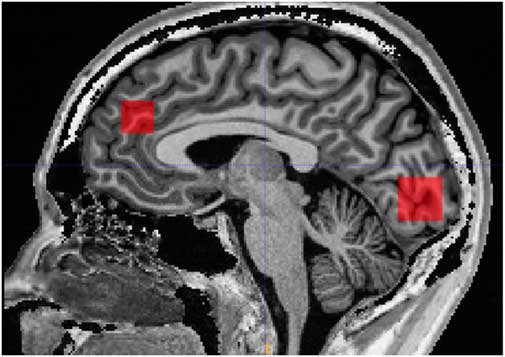

Scanning was performed on a 3 Tesla MR system (Siemens, Trio, Erlangen, Germany) with a body coil transmitter and a 32-channel receive head array. Data were acquired from a 30×15×15 mm voxel located in PFC and a 25×20×20 mm voxel located in OCC. A structural T1-weighted MPRAGE image (TR/TE 2420/4.58 ms, 1 mm isotropic resolution, scan time 10 min and 55 s) was acquired and used for manual positioning of the voxels and subsequent tissue segmentation. The PFC voxel was positioned just superior to genu of corpus callosum with the long axis along the right/left direction. The occipital voxel was oriented parallel to the occipital bone and just above the tentorium (Fig. 1).

Fig. 1 Illustration of prefrontal and occipital voxel placement.